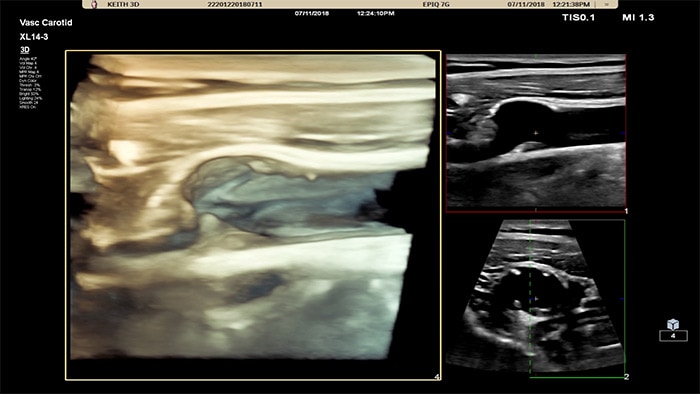

L’interface utilisateur 3D/4D permet également de générer un moulage du vaisseau en utilisant les flux de données. L’image du vaisseau 3D permet la visualisation directe du flux pour une analyse plus approfondie des états sténosés ou tortueux. Atout majeur : la visualisation 3D/4D de haute qualité de l’anatomie vasculaire constitue un outil de communication idéal pour faciliter la prise de décision clinique parmi les professionnels de la santé et améliorer la consultation avec les patients afin de les aider à comprendre leur état.

La sonde xMATRIX XL14-3 intègre 56 000 éléments remarquables, chacun connecté à un microcanal séparé. La sonde XL14-3 offre une focalisation électronique multidimensionnelle pour une imagerie échographique en coupes ultrafines de l’anatomie vasculaire et de la morphologie de plaque. Atout majeur : une fiabilité du diagnostic exceptionnelle lors de l’évaluation d’une sténose et d’une plaque vulnérable.

La sonde xMATRIX XL14-3 offre une imagerie xPlan qui va au-delà de l’approche conventionnelle des examens vasculaires, en fournissant des images en temps réel, simultanément dans des plans longitudinaux et transversaux. Atout majeur : avec l’imagerie xPlan, il n’est plus nécessaire de faire pivoter la sonde pour obtenir des vues orthogonales. Un simple mouvement de la boule de commande permet d’obtenir une évaluation anatomique complète, ce qui permet de gagner du temps lors de l’examen.